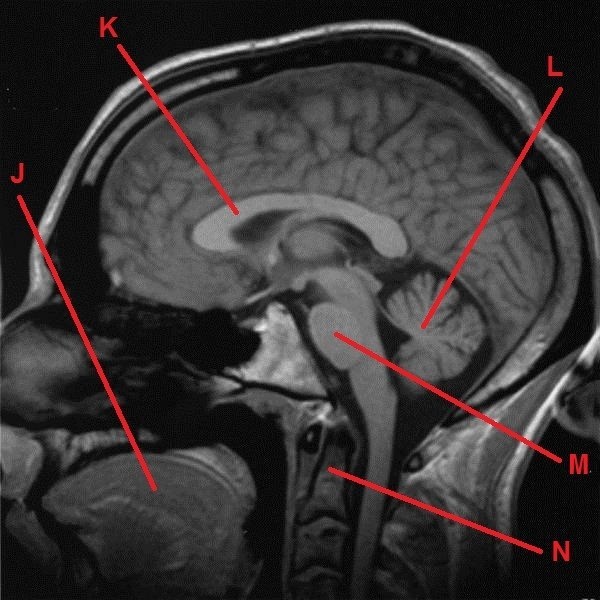

A dál co potřebujete k získání finálních souřadnic? Trocha z té zdravotnické praxe. Správný geokačer má silně vyvinutý smysl pro všímání si detailů, skrytých souvislostí a tak podobně. Princip je jednoduchý. Nepůjde o žádnou kdoví jak složitou matematickou šifru s IT podtextem. V budoucích několika minutách, hodinách či dnech se z Vás stanou radiologové (lékaři zabývající se zobrazovacími technikami) a anatomové. Tak Vás jistě nepřekvapí několik obrázků, na kterých bude vyznačen útvar, který musíte poznat a latinsky (pokud jiným jazykem, tak Vás na to upozorním) pojmenovat. Myslím, že vše bude jasné. Tak jdeme na to…

J - počet písmen v názvu útvaru (latinsky, 1 slovo)

K - počet písmen v názvu útvaru (latinsky, 2 slova)

L - počet písmen v názvu útvaru (latinsky, 1 slovo)

M - počet písmen v názvu útvaru (latinsky, 2 slova)

N - počet písmen v názvu útvaru (latinsky, 2 slova)